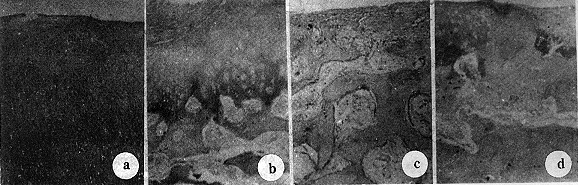

实验组及自体对照组新生组织表面平滑完整,与周边正常软骨及缺损基底部连接完全。两者新生组织都为软骨组织,PAS染色光镜下基质均红染,软骨细胞形态典型,位于软骨陷窝内。空白对照组新生物由纤维组织和幼稚软骨组成。新鲜对照组部份由纤维肉芽组织充填,未见软骨细胞(图2)。统计学比较实验组与自体对照组各指标均无显著差异(P>0.05),而与空白对照组及新鲜对照组主要指标均有显著差异(表2)。

图2 缺损修复的组织学特点(×200)

a、b分别为自体对照组和实验组,缺损被透明样软骨组织修复,PAS染色下基质红染,软骨陷窝内软骨细胞形态典型 c、d分别为空白对照组及新鲜对照组,前者缺损未修复,后者为肉芽组织